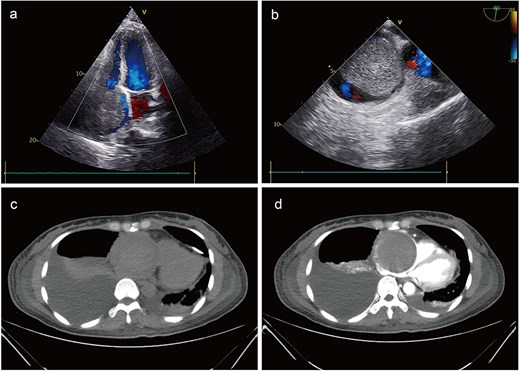

A 41-year-old female was admitted to our hospital with chest tightness and dyspnea for the past 2 weeks. Physical examination revealed bilateral lower limb edema without cardiac murmurs or jugular venous distention. Laboratory findings were notable for hypoalbuminemia (30 g/L) and an elevated D-dimer level (6.99 mg/mL), without remarkable blood routine examination and serum chemistry. Electrocardiography demonstrated sinus tachycardia and low-voltage complexes (Fig. 1). Echocardiography identified a large, well-demarcated hypoechoic mass (82 × 54 × 58 mm), nearly occupying the entire right atrial cavity (Fig. 2a and b). Contrast-enhanced computed tomography confirmed right pleural effusion and a right atrial occupying lesion (Fig. c and d). Subsequent right thoracentesis revealed exudative fluid with no evidence of malignancy on cytological examination. Further metabolic imaging with PET-CT (Fig. 3a and b) and PET-MR (Fig. 3c and d) demonstrated a hypermetabolic soft tissue mass within the right atrium, highly suggestive of primary cardiac angiosarcoma, with no signs of distant metastasis.

Preoperative imaging. Echocardiography identified a large mass, nearly occupying the entire right atrial cavity (a) and (b). Contrast-enhanced computed tomography showed a right pleural effusion and a right atrial occupying lesion (c) and (d).